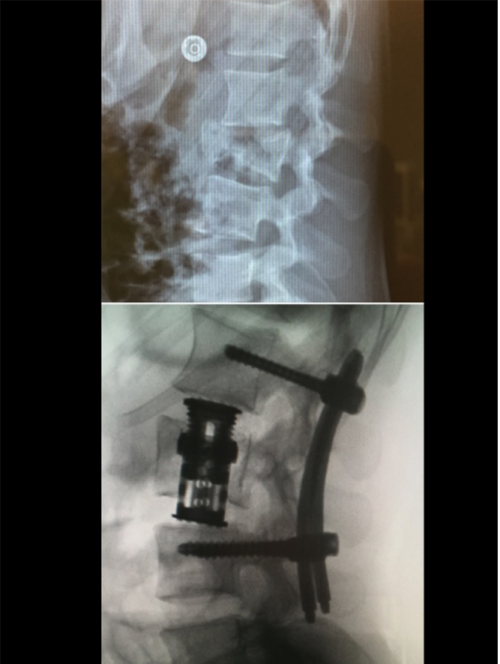

Pour certains types de fractures, la réalisation d’une expansion intra-somatique vertébrale est recommandée. Par un abord minimal invasif, on réalise la mise en place d’un implant au cœur de la vertèbre, SpineJack® dans notre exemple (Figure 3). Cet implant est ouvert par le chirurgien au cours de la procédure, ce qui permet une réduction de la fracture avec une stabilisation de l’intérieur. La consolidation est obtenue avec l’ajout de ciment chirurgical dans la vertèbre. Les suites opératoires pour ce type de procédures sont rapides, l’hospitalisation est courte et le patient retrouve une autonomie permettant de reprendre rapidement certaines activités (Figure 4).

Figure 3 : Procédure d’expansion vertébrale type SpineJack® :

-

Mise en place des implants dans la fracture.

Expansion de l’implant dans la vertèbre.

Radiographie en fin de procédure après injection de ciment chirurgical.